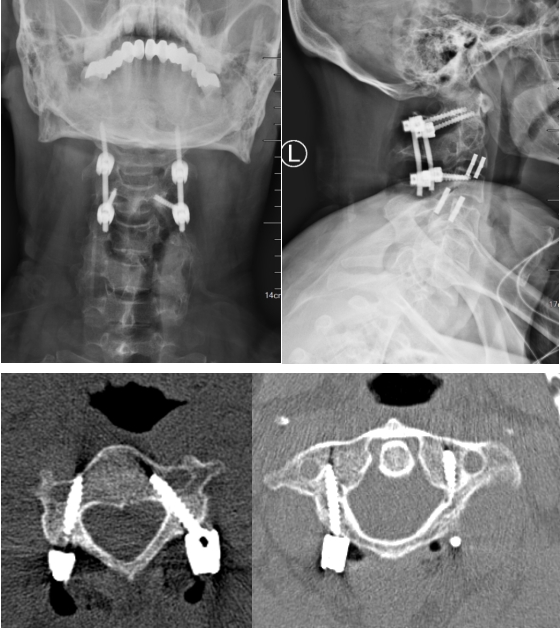

CT图像清晰显示患者C2齿状突骨折,并有移位

患者颈椎术后复查,置钉精准,内固定可靠